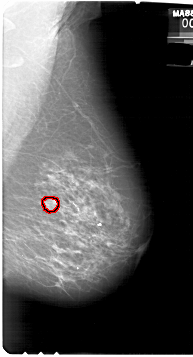

A_1827_1.LEFT_CC

FILE: A_1827_1.LEFT_CC.OVERLAY

TOTAL_ABNORMALITIES 1

ABNORMALITY 1

LESION_TYPE MASS SHAPE IRREGULAR MARGINS SPICULATED

ASSESSMENT 5

SUBTLETY 5

PATHOLOGY MALIGNANT

TOTAL_OUTLINES 2

BOUNDARY

CORE